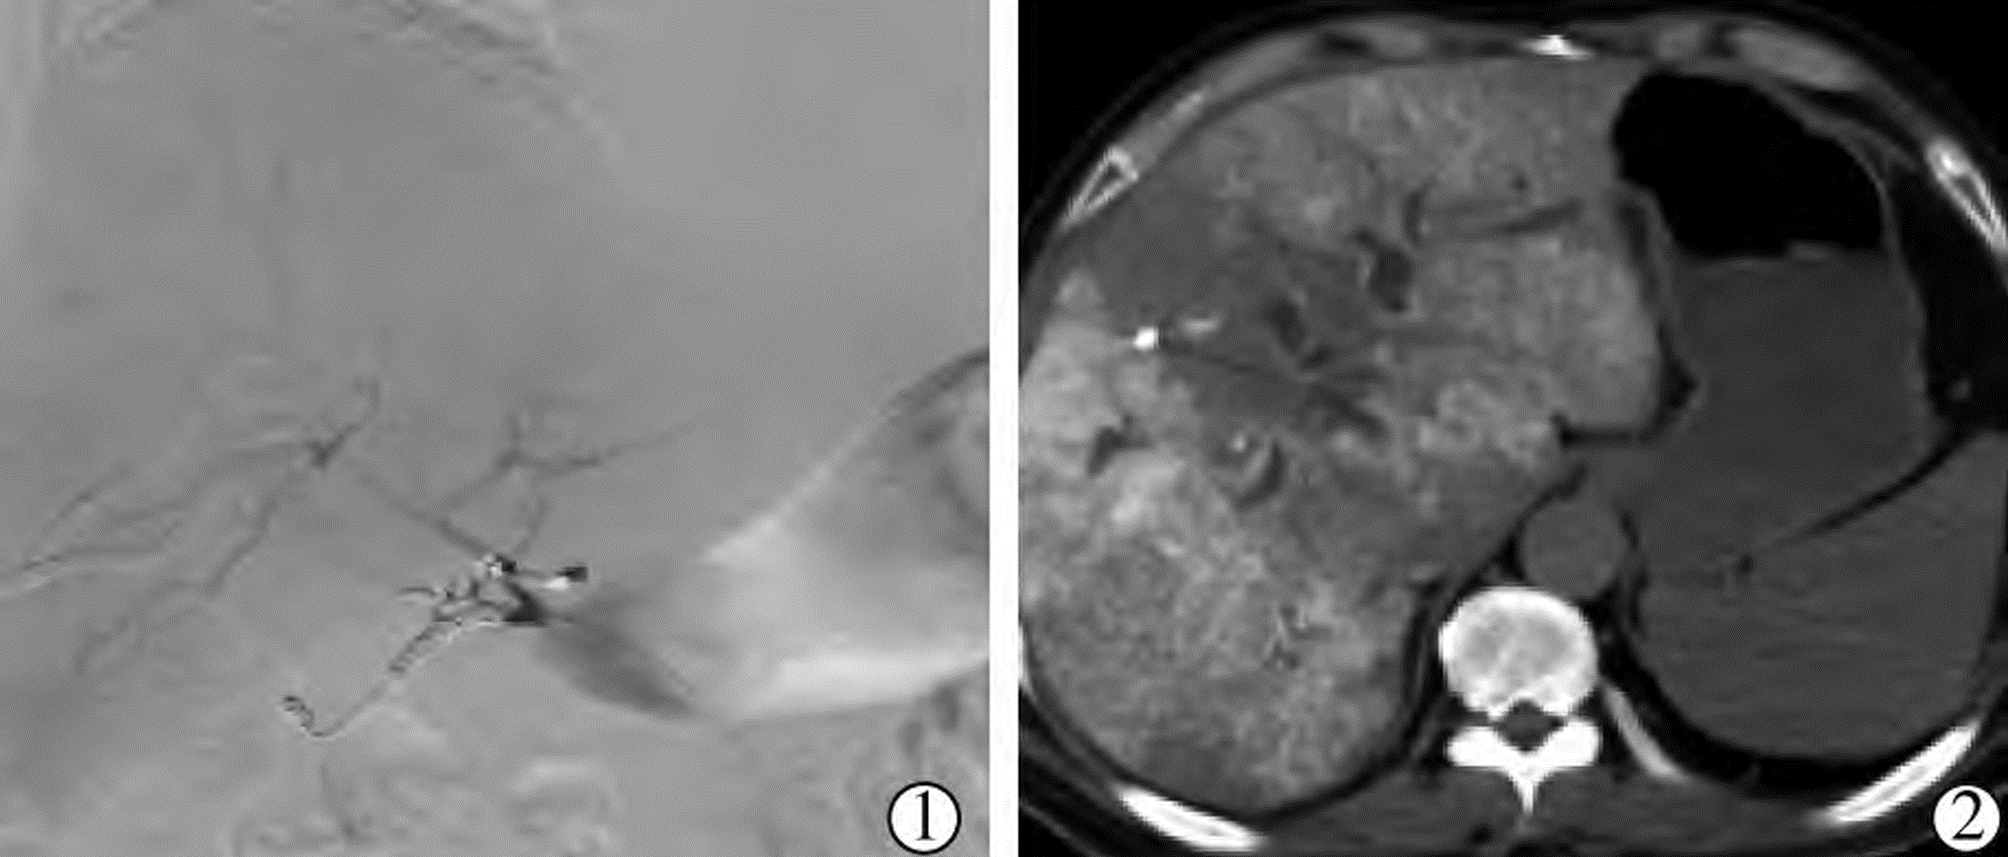

图 1 肝外血流再分布术

注:▲①腹腔动脉造影示胃右动脉(白虚线箭)从肝左动脉起始部发出,副胃左动脉(白实线箭)从肝左动脉二级分支处发出;②采用微弹簧圈超选择行胃右动脉和副胃左动脉(黑虚线箭)栓塞,胃十二指肠动脉(gastroduodenal artery,GDA)固定管头时栓塞(橙色箭),经药盒留置导管行肝动脉造影显示肝动脉分支显示完全,未见胃肠道动脉分支显示;▲③腹腔动脉造影示肝固有动脉发出十二指肠后上动脉(白实线箭)和胃右动脉(白虚线箭);④采用微弹簧圈超选择行胃右动脉和十二指肠后上动脉(黑虚线箭)栓塞,GDA固定管头时栓塞(橙色箭),经药盒留置导管行肝动脉造影示肝动脉分支显示完全,未见胃肠道动脉分支显示;▲经胃左动脉逆行栓塞胃右动脉:⑤经胃左动脉(白虚线箭)逆行超选择微导管至胃右动脉起始部(白实线箭)造影示胃右动脉;⑥微弹簧圈栓塞胃右动脉(黑实线箭),经药盒行肝动脉造影示胃右动脉闭塞,肝动脉显示完全。

Figure 1. Extrahepatic blood flow redistribution